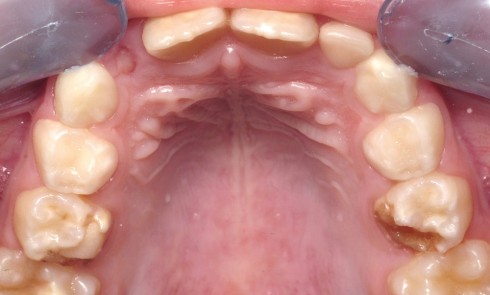

Les couronnes pédiatriques préformées métalliques (CPPm) sont indiquées sur les molaires temporaires dont le délabrement intéresse au moins deux faces,...

Les anomalies de structure des dents temporaires se manifestent par des atteintes très diverses : des anomalies de teinte, de morphologie,...